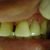

"Devolvendo a Estética Ii" Excelência da minha Técnica.dente 22.

Pcte sexo feminino, 49 anos, foi realizado tratamento estético dente 22. Pcte marcou novo horário para avaliaçao e se possível iniciar dentística cosmética em anteriores superiores.... Leia mais